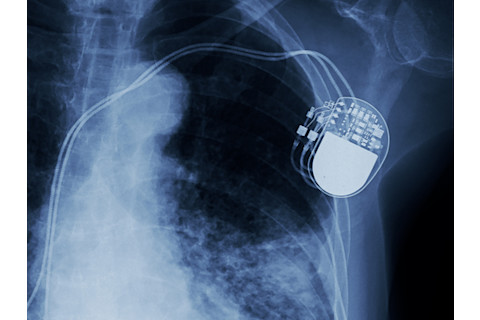

The Pacemaker

Credit:(ChooChin/Shutterstock)

Engineer and inventor Wilson Greatbatch created the first implantable pacemaker in 1958. It was actually the result of an accident. While working on an oscillator, he used the wrong part. This led to the machine emitting a steady electrical pulse — which he realized could be used for heart regulation. And with that, the first implantable pacemaker had its start. Greatbatch was a talented inventor, having been granted over 325 patents throughout his career. His innovative engineering skills led to him also inventing a corrosion-free lithium battery to be used in the implantable pacemaker. Prior to the implantable pacemaker, the machinery had to use an external power source the size of a television, and it was painful for patients. Because of the millions of lives saved by his invention, his pacemaker was recognized in 1985 as one of the 10 greatest engineering contributions to society of the last 50 years by the National Society of Professional Engineers.